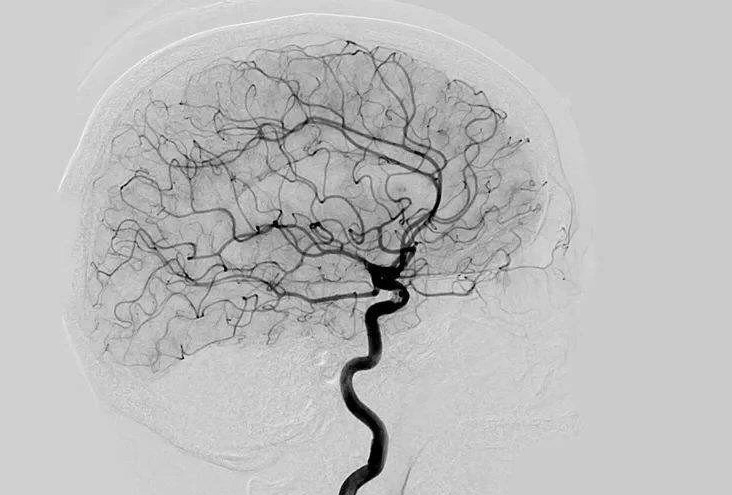

Digital Subtraction Angiography 血管造影機應(yīng)注意什么?

Digital Subtraction Angiography 血管造影機又稱數(shù)字減影血管造影機,是通過電子計算機進(jìn)行輔助成像的血管造影方法,應(yīng)用計算機程序進(jìn)行兩次成像完成的。在注人造影劑之前,第一次成像工作,圖像轉(zhuǎn)成數(shù)字信號儲存,注人造影劑后,再次成像并轉(zhuǎn)換成數(shù)字信號,兩次數(shù)字相減,消除相同的信號,得到只有造影劑的血管圖像。臨床主要應(yīng)用于冠心病、心律失常、瓣膜病和先天性心臟病的診斷和治療。